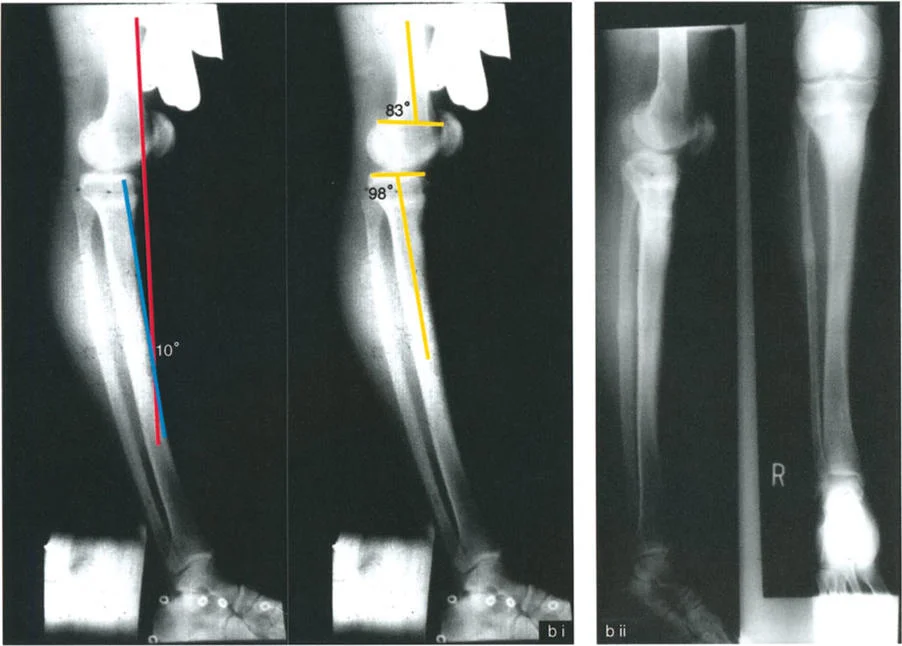

- حالة مريضة تبلغ من العمر 24 عامًا عانت من كسر في الفخذ في سن 12 عامًا، وعولجت بالشد. تسبب دبوس الشد في توقف نمو جزئي في الجزء القريب من عظم الساق، مما أدى إلى ارتداد ظنبوبي.

2. التصوير الشعاعي (الأشعة السينية):

تُعد الأشعة السينية ضرورية لتقييم التشوهات العظمية في المستوى السهمي. يتم التقاط صور شعاعية جانبية (Lateral X-rays) للركبة في وضعيات مختلفة (تمدد كامل، انثناء).

زوايا القياس الهامة:

- زاوية الانحناء البعيدة للفخذ (PDFA - Posterior Distal Femoral Angle): تقيس زاوية الجزء السفلي من عظم الفخذ. القيمة الطبيعية حوالي 84 درجة. الزيادة في هذه الزاوية (أكثر من 84 درجة) تشير إلى ارتداد فخذي.

- زاوية الانحناء القريبة للظنبوب (PPTA - Proximal Posterior Tibial Angle): تقيس زاوية الجزء العلوي من عظم الساق. القيمة الطبيعية حوالي 80 درجة. الزيادة في هذه الزاوية (أكثر من 80 درجة) تشير إلى ارتداد ظنبوبي.

- مركز دوران الزاوية (CORA - Center of Rotation of Angulation): يتم تحديد هذا النقطة على الأشعة السينية لتحديد مكان التشوه العظمي بدقة، وهو أمر بالغ الأهمية لتخطيط عملية قطع العظم.

- الركبة الارتدادية بسبب الارتداد الظنبوبي:

- إذا كانت درجة فرط التمدد (HE) تساوي درجة الارتداد الظنبوبي (PPTA > 80°)، فهذا يعني أن التشوه كله ناتج عن عظم الساق.

- في هذه الحالة، يكون مركز CORA في الجزء القريب من عظم الساق.

- إذا كانت درجة فرط التمدد (HE) تساوي درجة الارتداد الظنبوبي (PPTA > 80°)، فهذا يعني أن التشوه كله ناتج عن عظم الساق.